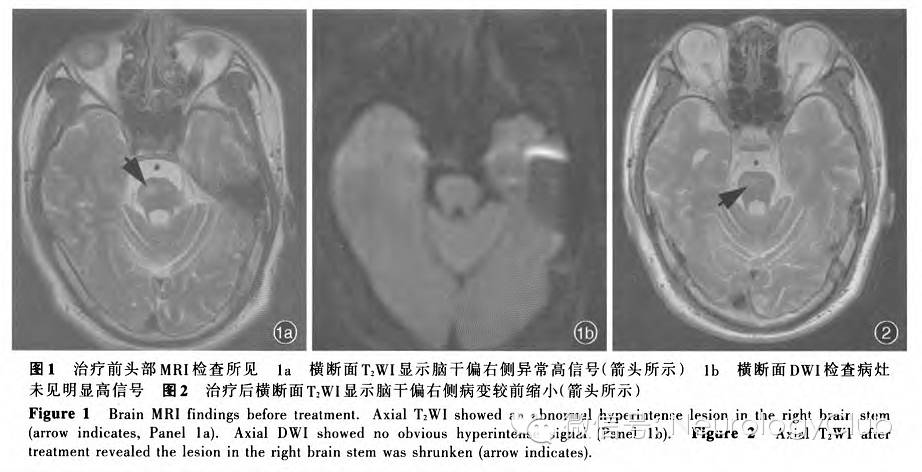

患者男性,34岁,主因反复左侧肢体无力1年余,于2015年3月25日入院。患者自2013年9月无明显诱因突发左下肢无力、踩地不实感和行走不稳,伴头晕,症状持续存在。外院头部MRI检查显示右侧丘脑长T1、长T2信号,以“脑血管病”治疗数日(具体方案不详)后症状逐渐缓解,但遗留行走缓慢。至2013年底逐渐出现言语模糊、饮水呛咳,伴记忆力减退、性格暴躁、懒散等精神症状,持续未缓解;外院复查头部MRI显示右侧丘脑病灶较前明显缩小,故未予特殊处理。6个月前突发左侧肢体无力、行走时左侧拖步,外院头部MRI检查显示右侧大脑脚、桥脑长T2信号,未予特殊处理,症状自行缓解,遗留左侧肢体无力,生活虽可自理但逐渐出现大小便失禁。1个月前再次出现左侧肢体无力加重,行走需拄拐或他人搀扶。为求进一步诊断与治疗,至我院就诊,头部MRI检查显示右侧丘脑、脑干多发小斑片状稍长T2信号(图1),遂以“神经白塞综合征;脑梗死待查”收入院。患者自发病以来,精神、饮食、睡眠尚可,体重无明显变化。

治疗方案为予以甲泼尼龙80mg/d、环磷酰胺0.20g(隔日1次)静脉滴注,连续治疗2周后改为甲泼尼龙48mg/d口服并规律减量;治疗期间复查实验室指标血清丙氨酸转氨酶水平显著升高(200U/L),考虑与环磷酰胺有关,改为硫唑嘌呤50mg/d口服和保护肝功能治疗[多烯磷脂酰胆碱胶囊456mg(3次/d)口服]。住院期间,间断鞘内注射甲氨蝶呤10mg和地塞米松10mg,并多次复查乙型肝炎病毒DNA<10^3拷贝/ml,暂未行抗病毒治疗。连续治疗15d后,临床症状明显好转,左上肢肌力恢复至5级、左下肢5级,再次行头部MRI检查,脑干和丘脑病灶较前缩小(图2),遂出院。

神经白塞综合征可分为实质性和非实质性,实质性以脑(膜)炎为主要表现,主要累及小血管,尤其是小静脉,光学显微镜下可见炎性细胞浸润脑干、基底节、丘脑和白质为实质性神经白塞综合征好发部位,尤以脑干受累常见,该例患者以脑干受累为主,影像学表现为急性期病灶呈长T1、长T2信号,DWI可见扩散指数升高,无明显高信号;急性期后病灶可明显缩小甚至消失,表明病变以小静脉淤血、组织水肿为主,而非动脉闭塞所致,可资与脑梗死相鉴别。非实质性神经白塞综合征以血管受累为主,约见于20%的患者,静脉窦血栓形成为其常见表现,亦可见颅内动脉瘤的报道

该例患者病程中反复出现痛性口腔溃疡、双眼葡萄膜炎,可疑外生殖器溃疡,以及反复出现复发-缓解的局灶性神经功能缺损,并以锥体束和脑干神经核团受累为主;影像学表现为以脑干为主、延伸至间脑的长T2信号,DWI无明确高信号改变;脑脊液检测显示以淋巴细胞为主的炎症反应,同时存在10%的中性粒细胞;经激素和免疫抑制剂治疗后,临床症状和影像学表现均有改善,为典型神经白塞综合征。通过对患者例诊断与治疗经过的复习,进一步加深对神经白塞综合征的认识,增加临床经验。